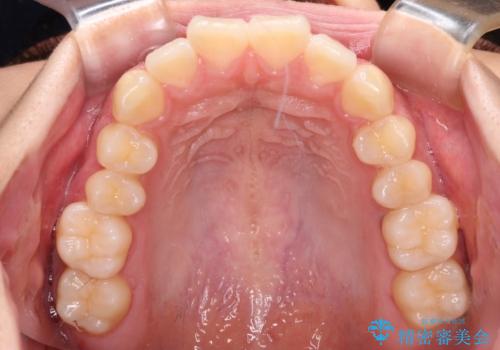

口元の印象が劇的に解消され、気にしていたガミースマイルも図らずも改善することができました。

上下前歯が嘴のように前方に突出しており、唇が閉じにくい状態であったため、上下左右の第一小臼歯4本を抜歯して、口元の突出感を改善することとしました。